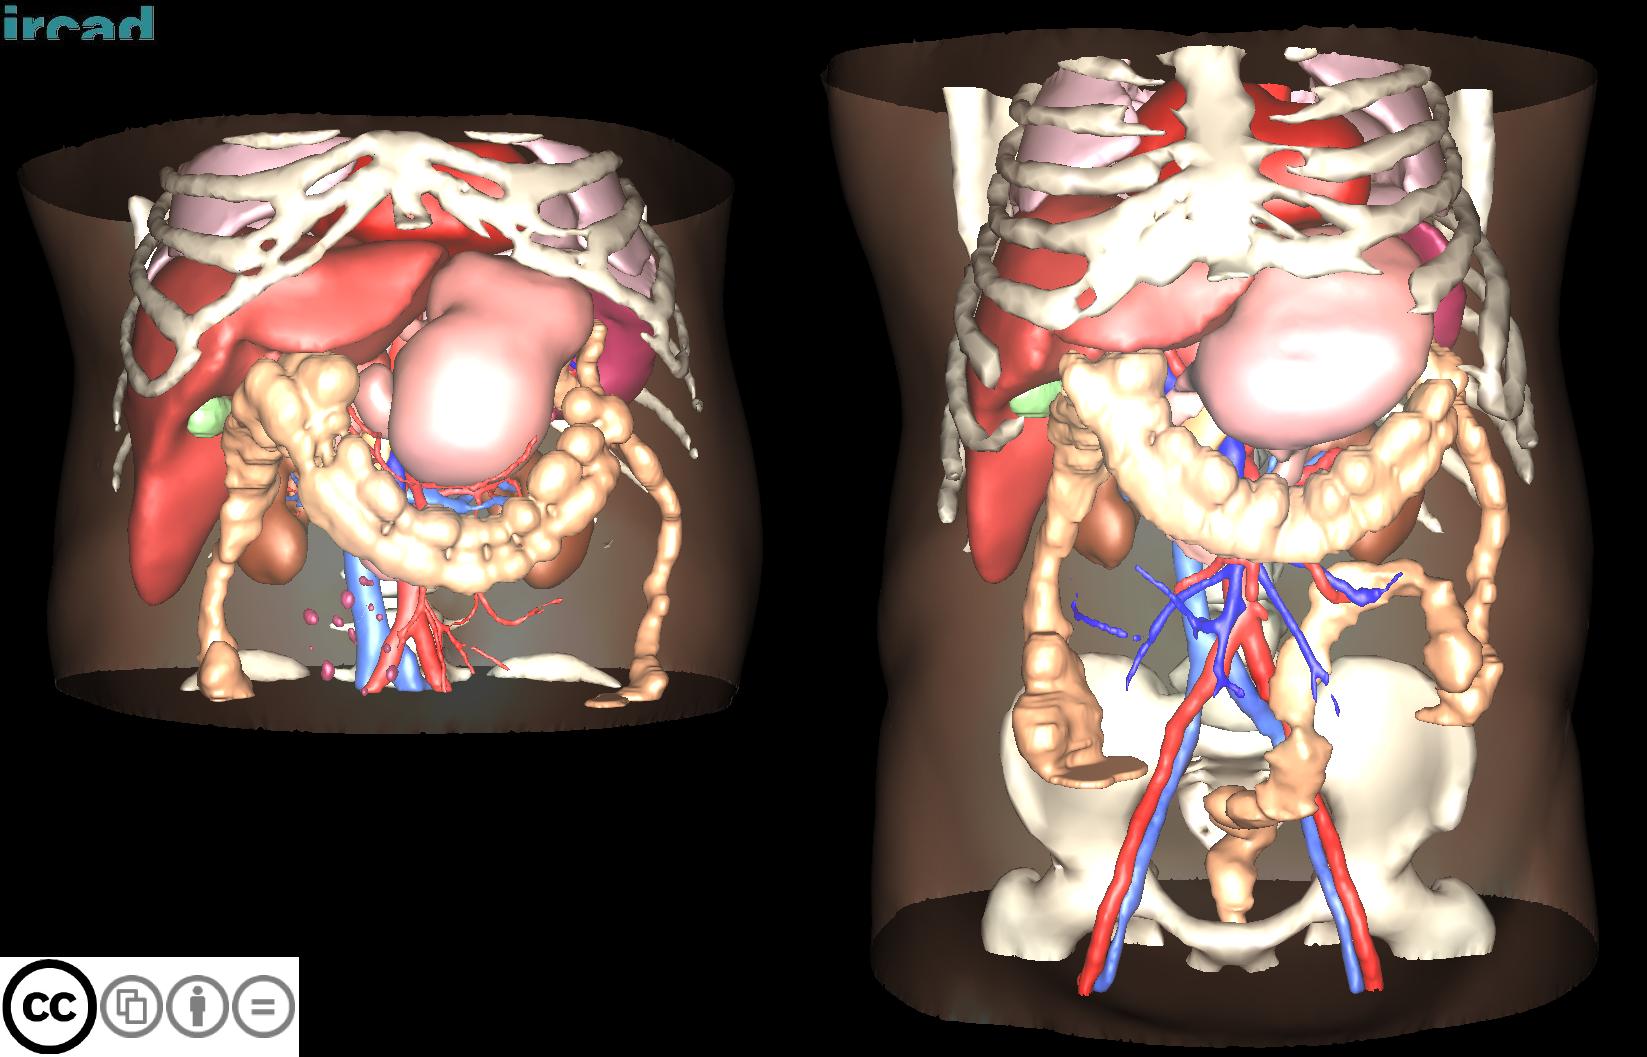

3D-IRCADB

| 名称 | 标注内容 | 类型 | 模态 | 数量 | 标签格式 | 文件格式 |

|---|---|---|---|---|---|---|

| 3D-IRCADb 01 02 | 肝脏/肝肿瘤 | 分割 | CT | 20+2 | surface mesh | dcm |

3D-IRCADb是比较早的一个数据集,有两个子集,分别包含20组和2组CT片子。